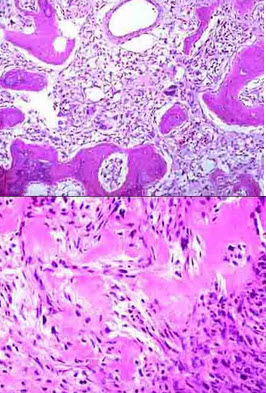

15、单项选择题

患者,男,60岁,左侧鼻翼处有一不规则形褐色肿物,表面有溃疡形成,切除肿物送检。

大体如图,镜检如图所示,正确的诊断是()

A.低分化鳞状细胞癌

B.皮内痣

C.基底细胞癌

D.低分化腺癌

E.黑色素瘤

点击查看答案